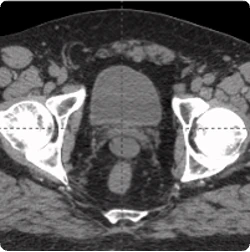

215 cc prostate post-CT showing BioProtect Balloon Spacer, prostate, and rectum.

Post-CT

Image courtesy of Dr. Shawn Zimberg, Radiation Oncologist.